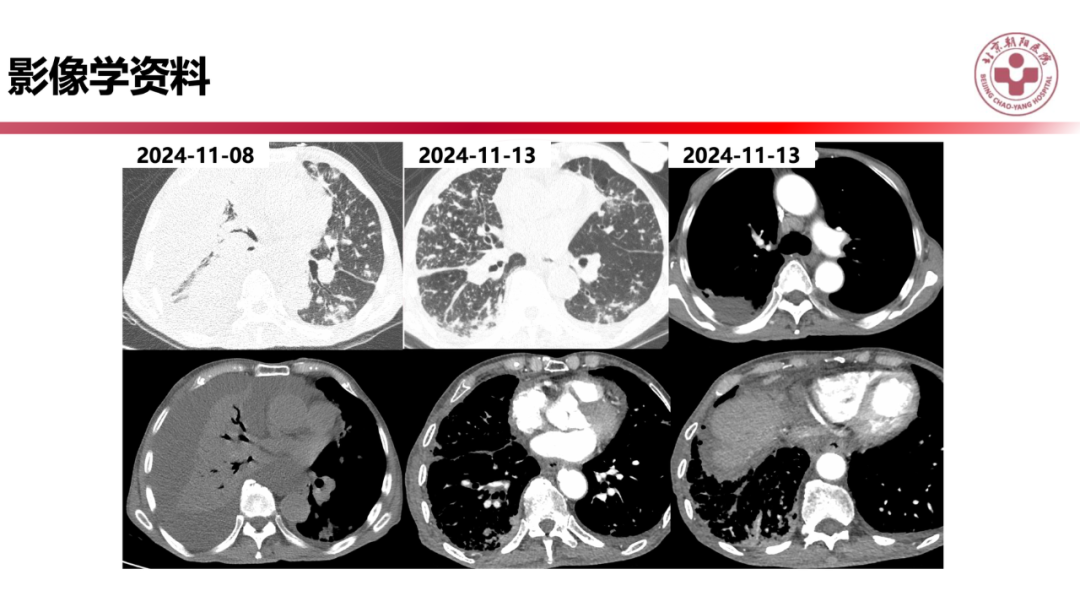

IgG4相关性肺疾病的诊断思路是什么?

来源:北京朝阳医院放射介入影像中心